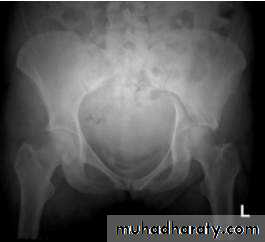

The golden role is to x ray the pelvis in every case of sever injure

and with femoral fracture to include both the hip and knee.Radiological examinations

X-R AP view we can see the dislocation with or without associated fracture posterior wall of the acetabulum,or fracture head of the femur,

And neck of femur.